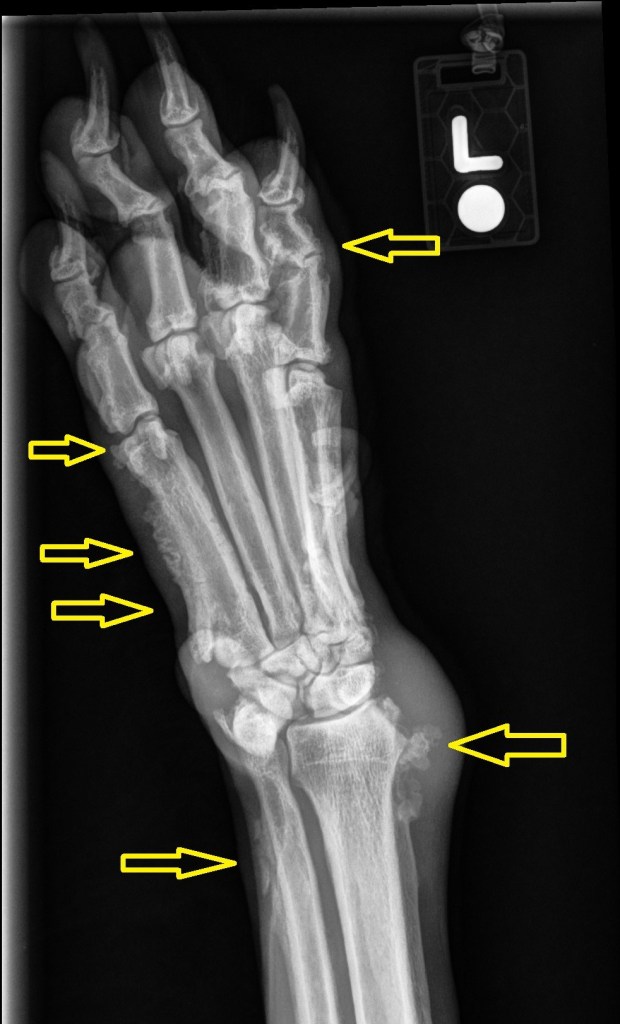

Findings:

Well-defined columnar/palisading periosteal new bone with swollen surrounding soft tissues can be seen along the abaxial surfaces of the diaphyses of the (bilateral) 2nd and 5th metacarpal bones (and the proximal and abaxial aspects of the adjacent proximal phalanges), the distolateral aspect of both ulna, distomedial aspect of both radii, and the medial aspect of both intermedioradial carpal bones.